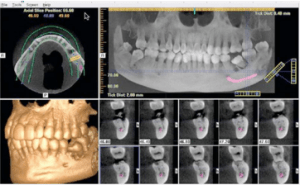

The patient is precisely placed in a comfortable position at the machine. The scan takes about 20 seconds to rotate around the head, obtaining nearly 600 distinct images. The focused x-ray beam reduces scatter radiation, resulting in better image quality. Once complete, the 3D image is immediately available for viewing and diagnosing. The scan produces a wide variety of views and angles that can be manipulated to provide a more comprehensive evaluation. One CBCT scan uses about 1/20th the radiation of a traditional head and neck scan at the hospital.